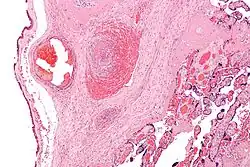

Одна из самых тяжёлых форм ДЦП, являющаяся следствием аномалий развития головного мозга, внутриутробных инфекций и перинатальной гипоксии с диффузным повреждением полушарий головного мозга. У недоношенных детей основной причиной при перинатальной гипоксии является селективный некроз нейронов и перивентрикулярная лейкомаляция; у доношенных — селективный или диффузный некроз нейронов и парасагиттальное поражение мозга при внутриутробной хронической гипоксии. Клинически диагностируется спастическая квадриплегия (квадрипарез; более подходящий термин[9], по сравнению с тетраплегией, так как заметные нарушения выявляются примерно одинаково во всех четырёх конечностях), псевдобульбарный синдром, нарушения зрения, когнитивные и речевые нарушения. У 50 % детей наблюдаются эпилептические приступы. Для данной формы характерно раннее формирование контрактур, деформаций туловища и конечностей. Почти в половине случаев двигательные расстройства сопровождаются патологией черепных нервов: косоглазием, атрофией зрительных нервов, нарушениями слуха, псевдобульбарными расстройствами. Довольно часто у детей отмечают микроцефалию, которая, разумеется, носит вторичный характер. Тяжёлый двигательный дефект рук и отсутствие мотивации исключают самообслуживание и простую трудовую деятельность.

При ДЦП на МРТ головного мозга может отмечаться корково-подкорковая атрофия, псевдопорэнцефалия, диффузное снижение плотности белого вещества.